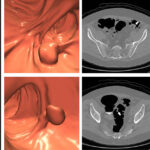

Aaron Eifler, MD and Sean Golden, MD are UW Interventional Radiology (IR) physicians who offer prostate artery embolization (PAE), a minimally-invasive treatment option for patients who seek relief from BPH but are unable or hesitant to undergo more invasive, surgical treatments like holmium laser enucleation of the prostate (HoLEP) and Transurethral resection of the prostate (TURP).